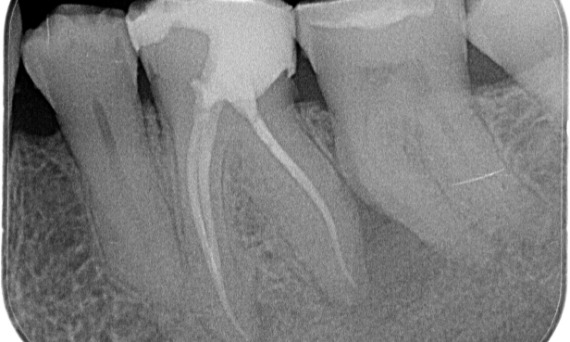

Prima: All’esame è stata riscontrata una lesione da carie sul primo molare inferiore destro. L’esame radiografico ha rivelato la vicinanza della lesione al corno pulpare e, combinandola con il disturbo principale, si è giunti alla diagnosi finale di pulpite cronica irreversibile.

Dopo: La cavità di accesso è stata effettuata nel modo più conservativo possibile. TruNatomy è stato il sistema prescelto a causa dell’età del giovane paziente. Dovevamo preservare il più possibile la dentina per aumentare la capacità del dente di superare il carico occlusale e aumentare la longevità del restauro finale.